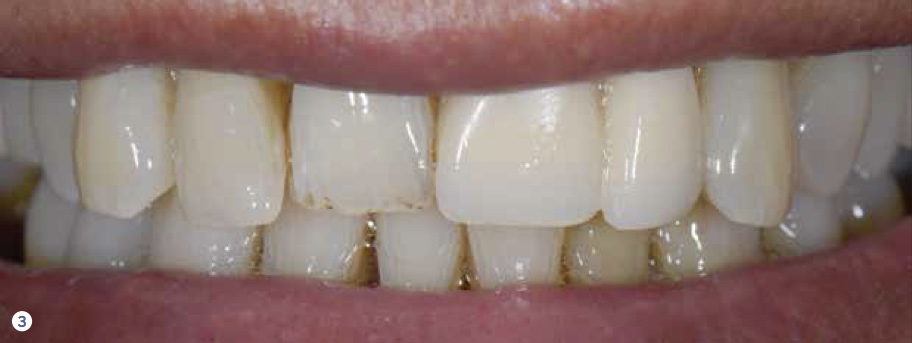

Fig 3. A 70+ year-old-man presented with a poorly designed anterior implant-supported restoration partially disguised by lip position and mobility.

Figure 3